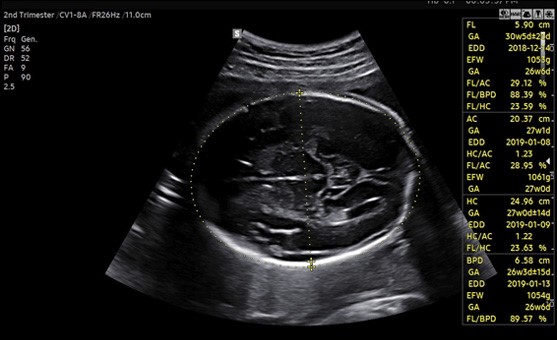

Подробно. Samsung Medison BiometryAssist™ выполняет автоматическое измерение и оценку размеров плода с точностью 97%[1] в один клик мыши, затрачивая на это примерно 85 миллисекунд. Такая скорость работы позволяет врачу принимать большее количество пациентов и уделять больше времени для общения с ними. ,

«Технология BiometryAssist™, созданная Samsung Medison – это полуавтоматическая система измерения и оценки размеров плода с точность 97-99%. Такая высокая эффективность позволяет использовать решение в современной клинической практике», – прокомментировал доктор медицинских наук, профессор Джа-Ён Квон (Ja-Young Kwon) департамента акушерства и гинекологии Медицинского колледжа Университета Йонсей в Сеуле, Корея.

[1] Источник: собственные тесты Samsung. Конфигурация системы: процессор Intel® Core ™ i3-4100Q с частотой 2,4 ГГц, 8 ГБ памяти; ОС: 64-битная Windows 10. Время измерения без использования OpenVINO составило 480 микросекунд. Время измерения с улучшениями OpenVINO составило 85 микросекунд.